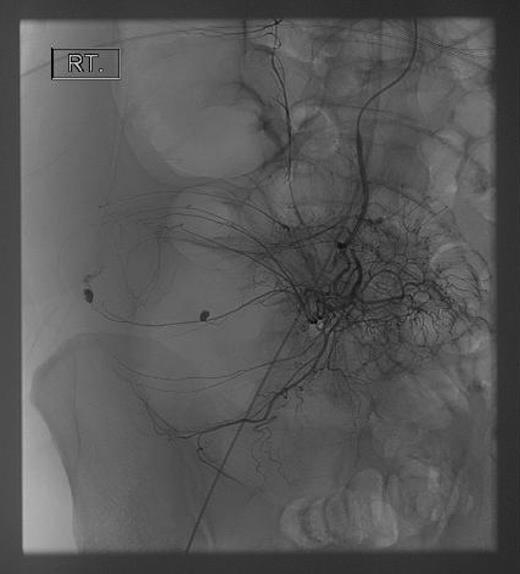

Seventy-two hours after starting his anti-tubercular therapy, he took a turn for the worse and was transferred to the ICU for ventilatory and inotropic support. He had ∼1 l of bleeding per rectum and dropped his haemoglobin (Hb) from 140 to 65 g/l. An oesophagogastroduodenoscopy showed no cause for upper GI bleeding. A CT abdomen + pelvis with contrast was performed, which showed a large (20 cm) inflammatory caecal mass with a moderate amount of intra-abdominal free fluid (Fig. 2). Selective angiography of the superior mesenteric artery demonstrated the bleeding point in the caecum and this was embolized superselectively with coils (Fig. 3).

His bleeding continues post-embolization, so a midline laparotomy was performed. The ascending colon was distended and very friable on mobilization. The posterior wall of the caecum was perforated and visibly the nidus of the bleeding (Fig. 4). The terminal ileum was normal and there was no gross lymphadenopathy. A right hemicolectomy was performed with primary stapled anastomosis.

Grossly enlarged and perforated caecum with a suction device demonstrating the depth of the cavity.